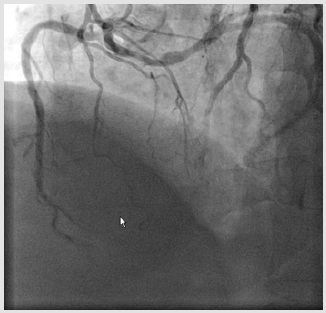

A 67-year-old man presented progressive chest pain after physical exertion for ten months, he was admitted to our hospital on November 6th, 2009. He suffered from diabetic mellitus and hypertension for eight years. Coronary angiogram was performed through trans-radial approach. An angiogram demonstrated a single coronary artery: the LMCA originating from the proximal of right coronary artery and then dividing into the left anterior descending artery (LAD) and the left circumflex artery (LCX). In LAO projection there was borderline lesions at the body of the LMCA, it was about 1.5cm lesions in length. There was mild narrowing in the mid of LAD segment, and the LCX, RCA were patent (Figures 1-3). As the lesions of LMCA are borderline, neither percutaneous coronary intervention (PCI) nor coronary artery bypass graft surgery (CABG) was performed, the patient was treated by oral medications including aspirin, nitroglycerine, atorvastatin and ACEI drugs. He was free of chest pain during a 24- month follow-up. In order to confirm the origin and course of the anomalous LMCA, a 64-slice computed tomography (MSCT) of the heart was performed on a 64-slice machine (Philips 64 Slice, Philips, Netherland) after 6 months of coronary angiography. The results showed the anomalous left main coronary artery originating from the proximal of the RCA, posterior to the aorta then taking an acute bend to course between the aorta and left atrium (Figures 4&5). The anomalous LMCA was classified as R-II P subtype.

Figure 1: LAO caudal projection shows the anomalous LMCA originating from the proximal of RCA and the lesion of LMCA.

Figure 3: LAO cranial projection demonstrates the borderline long lesion of left main coronary artery.